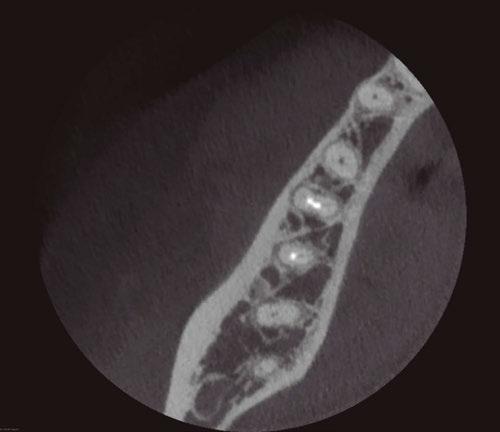

on the crest of the ridge in the region of teeth Nos. 15-25. While creating the incision, bleeding was noticed in the region of tooth No. 15 which intensified during the flap reflection (Figure 2). Bleeding was pulsatile, indicating an arterial bleed. Initially attempts to control bleeding included a pressure pack and ice pack, and the bleeder was isolated, and the vessel ligated (Figure 3). The bleeding could be controlled, and the procedure was completed by placing four Bioner implants (Bioner, Spain), size 4/10 mm. Sutures were placed, and patient was kept on basic medication for pain and infection control. Immediately after the surgery, the patient was advised to get a CBCT. As shown in Figure 4, a coronal view and Figure 4B (yellow arrows), the position of the artery can be seen.

Figure 1: Pre-op panoramic radiograph Figure 2 (left): Alveolar antral artery (AAA). Figure 3 (center): The artery has been ligated with suture. Figures 4A and 4B (right): CBCT post-implant placement and position of the artery coronally (top). 4B. Showing the position of alveolar antral artery (AAA) in relation to implant placement as indicated by the yellow arrows (bottom)